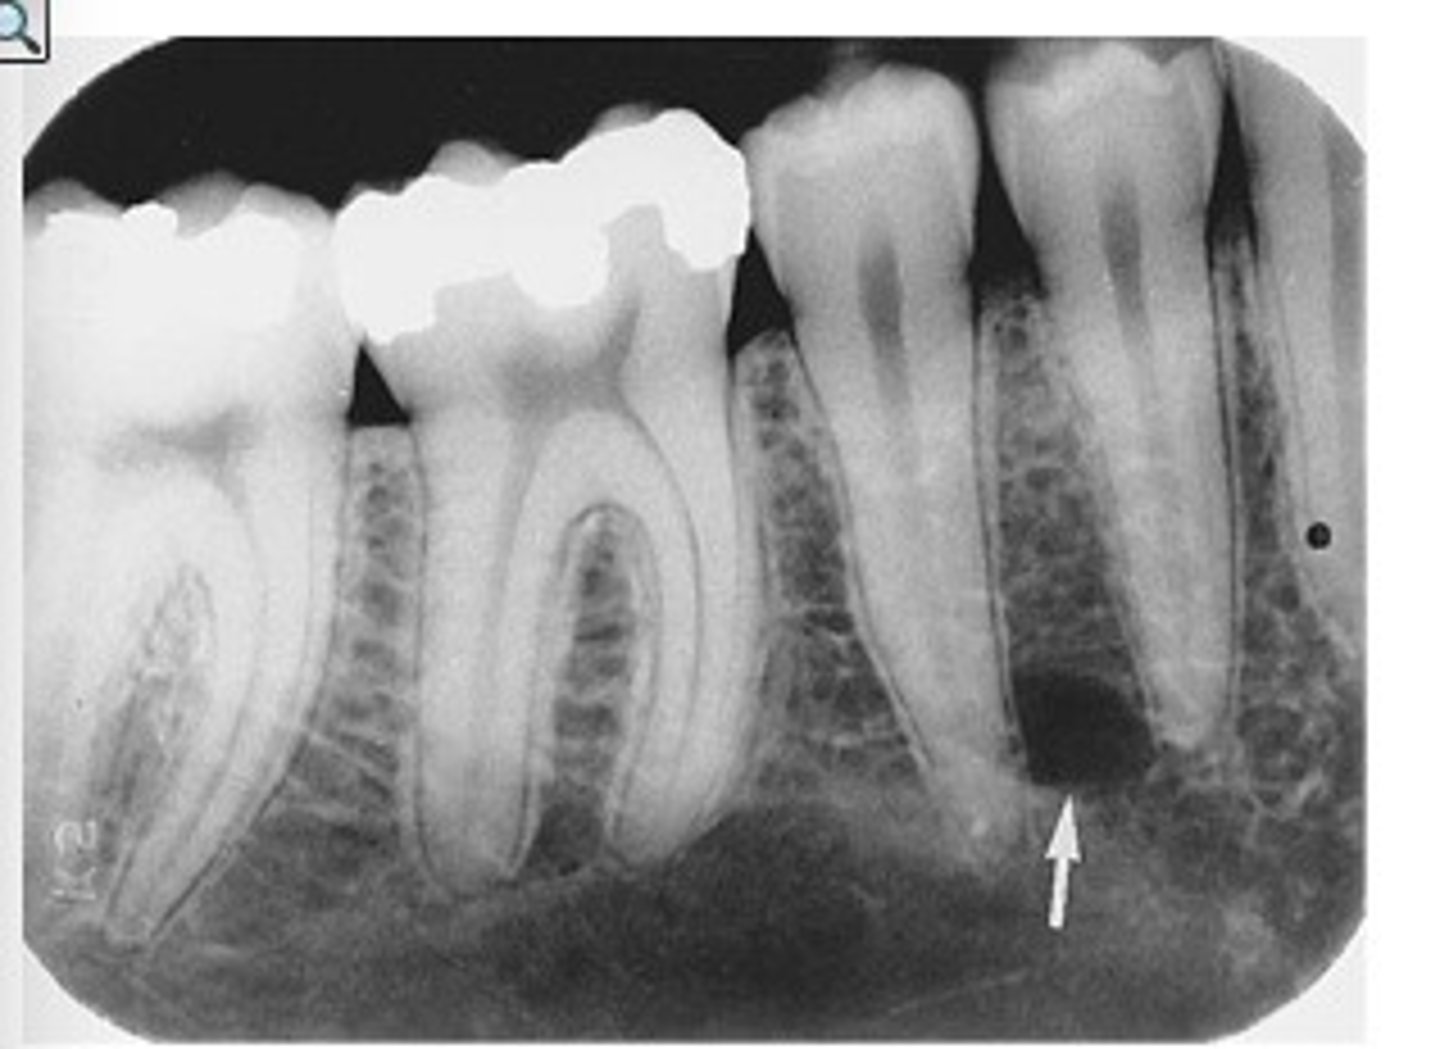

What are radiographic features of complex odontomas?

radiopaque mass

What is the treatment and prognosis for complex odontomas?

⢠treatment: surgical excision

⢠prognosis: excellent